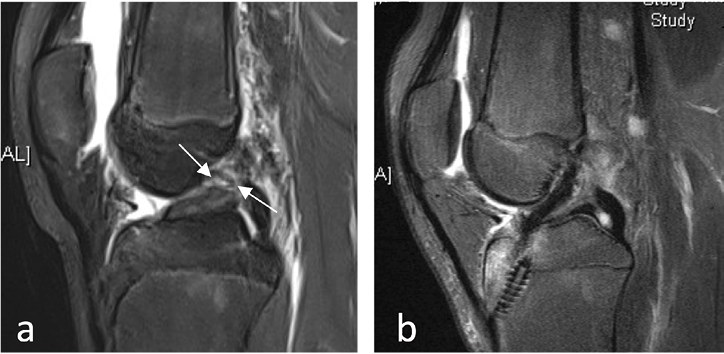

Die Therapie der isolierten Kreuzbandverletzung wurde lange Jahre diskutiert. Es wird heutzutage aufgrund der bekannten hohen Rate an Meniskusläsionen nach Kreuzbandläsionen bei Kindern (circa 50 % nach einem Jahr) eine zeitnahe Rekonstruktion empfohlen. In der aktuellen Literatur wird bei allen kompletten Rupturen des vorderen Kreuzbandes mit Knieinstabilität (Giving Way Zeichen) ein operativer Ersatz empfohlen um instabilitätsbedingte Meniskus- und Knorpelläsionen und damit der Gefahr der Früharthrose zu verhindern. Zudem konnten bisher keine relevanten Wachstumsstörungen aufgrund der Durchbohrung der Wachstumsfugen nachgewiesen werden unter der Voraussetzung einer Kind-adaptierten, schonenden Operationstechnik und Sehnenersatzplastik. Hierunter verstehen die Autoren eine Kreuzbandersatzplastik mittels Semitendinosussehne und einem steilen Bohrkanal, da es hierdurch zu einer flächenmäßig geringeren Beeinträchtigung der Fuge in Bezug auf die Fläche der Gesamtfuge kommt. Es erscheint eine Einzelbandplastik mittels Semitendinosussehne ausreichend und Bohrkanal und Sehne sollten den gleichen Durchmesser haben. Eine Fixation außerhalb der Fuge mittels Metallplättchen oder kurzen bioresorbierbaren Schrauben wird empfohlen [5–7] (Abb. 2).

Abb. 2: 15-jähriger Junge mit Z.n. Kniegelenkstrauma beim Fußball im Zweikampf, MRT mit a) intraligamentäre VKB- Ruptur (weiße Pfeile) und deutlichem intraartikulärem Erguss, operatives Vorgehen b) postoperative VKB Plastik mit bioresorbierbarer Schraube tibial (fugenübergreifend bei fast geschlossenen Wachstumsfugen)